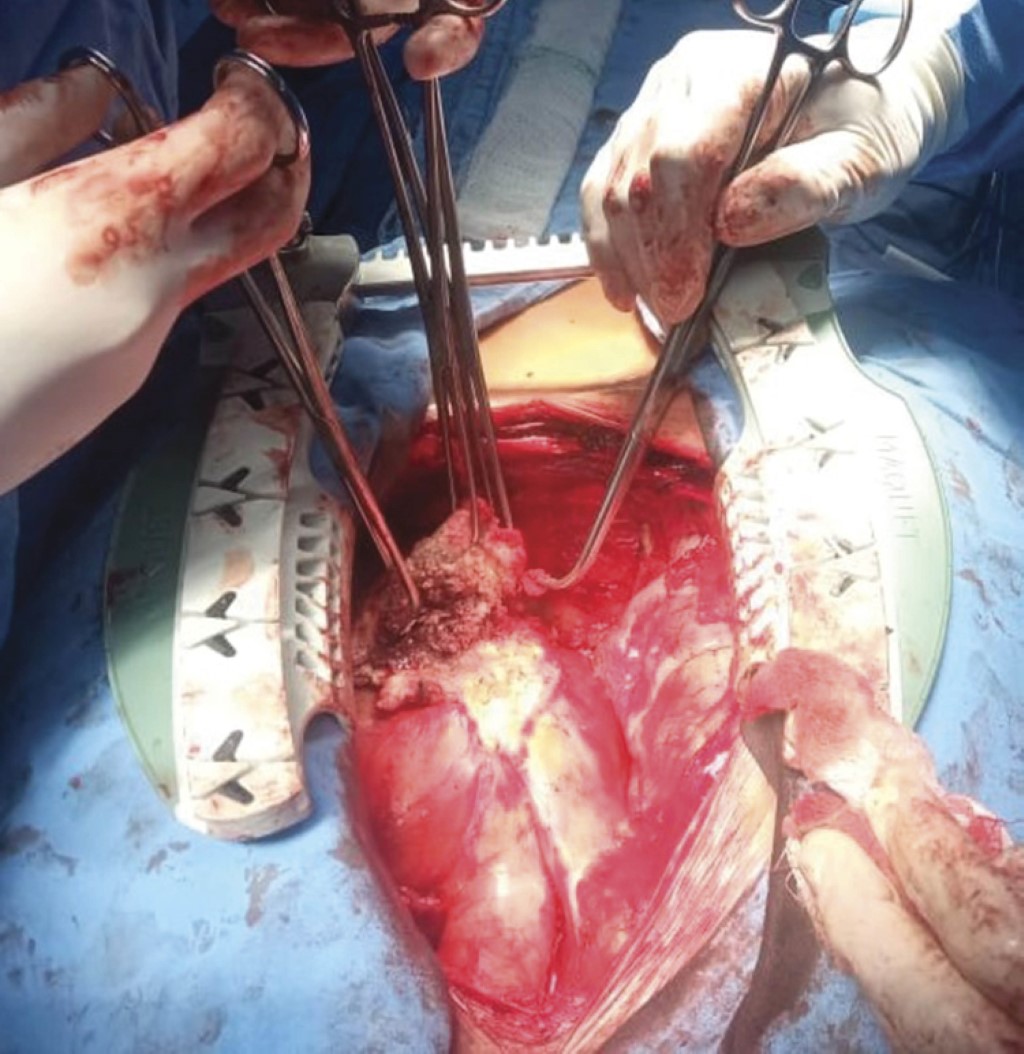

The patient was discussed in an internal committee at our hospital and accepted for pericardial tumor resection. A surgical procedure was scheduled with a median sternotomy approach, performing an interphrenic pericardiectomy without cardiopulmonary bypass. Findings included a thickened pericardium of 2 cm with severe calcification infiltrating the anterior wall of the right ventricle, pulmonary hilum, right atrium, and both venae cavae (Figure 2). There was a chronic-appearing hematoma of approximately 20 cc on the anterior wall of the right ventricle (Figure 3). There were no complications during the intervention, and the patient evolved favorably during his stay in intensive care.

The pericardium was resected, and part of the tumor was sent to pathology, which reported multifocal calcified granulomatous chronic pericarditis secondary to microconidia of Histoplasma spp. In the tissue sent to pathology after mass resection, not only inflammatory tissue but also microorganisms reaching the pericardium were found, which led to initiating antifungal treatment.5

Figure 2